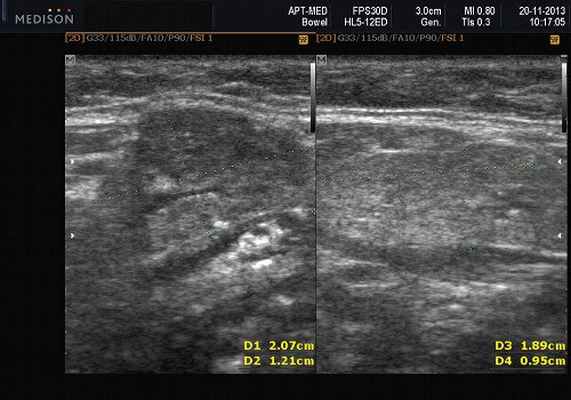

- обструктивные сиаладениты, развивающиеся при затруднении оттока слюны при обструкции выводного протока камнем (рис. 5-7) или сгустившимся секретом, а также вследствие рубцового стеноза протока. По распространенности процесса различают очаговый, диффузный сиаладениты и сиалодохит - воспаление выводного протока. Течение процесса может быть острым и хроническим;

Рис. 5. Камень протока поднижнечелюстной слюнной железы.

Рис. 6. Камень в паренхиме поднижнечелюстной слюнной железы.

Рис. 7. Камень в протоке поднижнечелюстной слюнной железы.